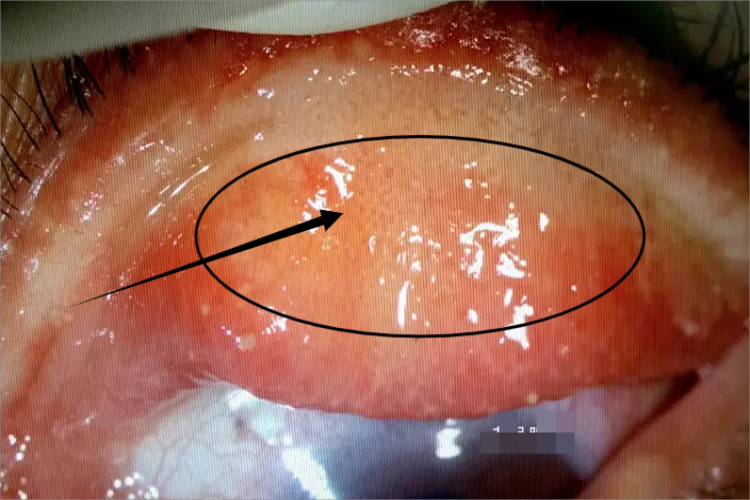

眼睑皮脂腺癌是常见的眼睑恶性肿瘤,可导致患处有斑,面积较小,微微隆起,边界清楚,常伴有局部异物感。